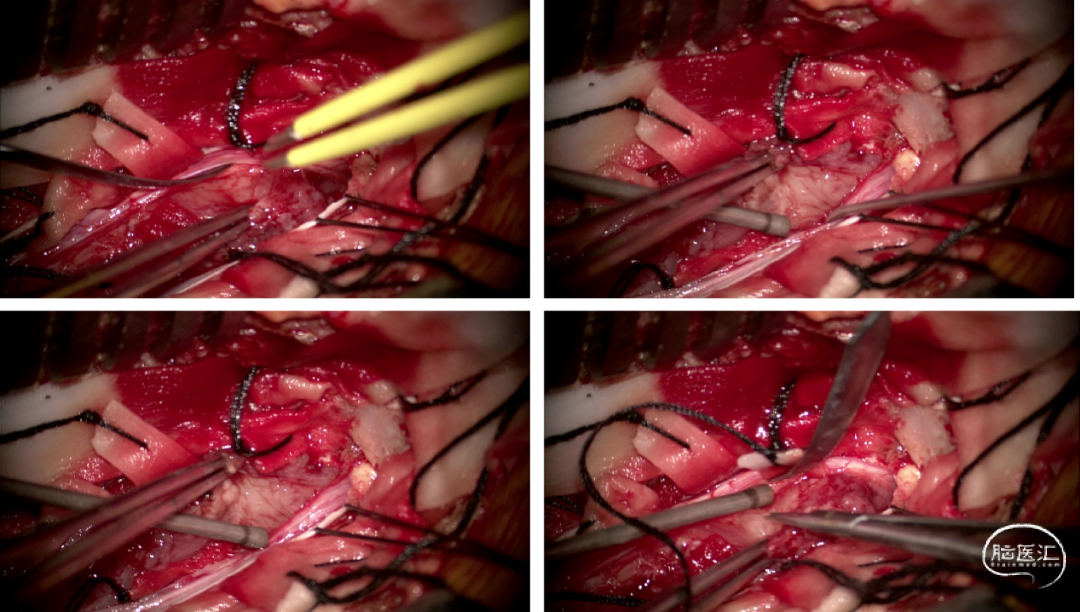

手术情况

硬脊膜张力高,脊髓向背侧膨出,与脊髓腹侧粘连紧密,肿瘤挤压脊髓,肿瘤边界分离,减少对胸髓的牵拉,降低了术后患者神经功能发生的概率,术后患者肢体麻木症状改善。